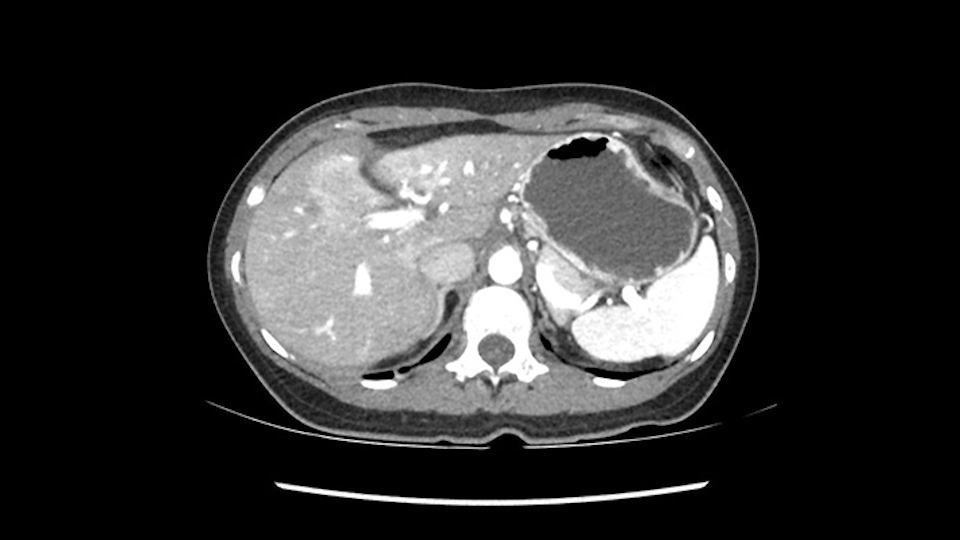

Hi my name is Steven Gallinger. I’m professor of surgery at the University of Toronto and a hepatobiliary and pancreatic surgical oncologist at the University Health Network. This patient is a 41-year old who we saw recently with chronic Hepatitis B who is untreated and noticed a protrusion in her upper abdomen and after a series of investigations was found to have this hypervascular liver lesion. Her alpha fetoprotein was about 26000 so the diagnosis really wasn’t in question. Although we did review the diagnostic imaging at our tumor boards last week and the consensus was that this is a hepatoma. The patient had good liver function, actually perfect liver function biochemically. Considering the location of this lesion and her age and alternative treatments, we felt that resection would be the best approach for this tumor.

So if we look at the CT scan, on the axial, it’s a larger lesion. It’s about 6 or 7 or 8 centimeters. So it does look a bit threatening in terms of its resectability but if you really drill down deeply into the anatomy, and I think the coronal [imaging] is even better, you can see that the entire mass is on the patient’s left side of the falciform ligament. So it’s really only a left-sided tumor and not even really a left-sided tumor because Segment 4 is uninvolved anatomically.

None of the parenchyma is affected and this tumor is very exophytic; like many Hepatitis B hepatomas; and otherwise is resectable with either a wedge resection part of Segment 2-3 or a formal left lateral segmentectomy.

As I review the CT scan, we have both arterial and venous phases, the tumor is obvious. But I’ll start by saying that the liver itself does not appear to be cirrhotic to my eye. It’s got a normal contour and allied to that, that I do not see evidence of portal hypertension. The spleen is normal, there’s no collateral vessels. The tumor itself, I measured maximally at about 11 centimetres in diameter and I’m told the alpha fetoprotein is very high (over 10000), which is entirely consistent with this being a solitary hepatocellular carcinoma that is very exophytic. It seems to emanate off the inferior margin of Segment 3 (because that’s the falciform). I’ll start by saying that this is not transplantable. The tumor exceeds our guidelines for transplantation, but it's likely resectable based on normal liver and no portal hypertension.

Hi my name is Sedat Karademir. I’m from Ankara Guven Hospital and I’m an HPB and transplant surgeon. We are discussing about the case I reviewed the CT of 41 year old lady with a suspected hepatoma in the left lateral segment. Presumably its Segment 3. It looks like a big tumor sitting exophytically mostly out of the liver and pressing on the surrounding organs, but it doesn’t look like any invasion there. In this situation, according to the venous and arterial anatomy, it looks like this will be a Segment 2 and 3 resection.

When you see the axial sections of the scan, you find it's a largely exophytic mass and its well-encapsulated. So this is typically true of a well-differentiated hepatocellular carcinoma. If you look at this, this is the gallbladder which is being displaced to the right and the mass is in the Sg4 of the liver, exophytic, projecting down. As it is coming down, it is also displacing the duodenum and the head of the pancreas which is being pushed towards the left and it's going right up to the cava, the start of the anterior surface of the cava. Obviously getting a lot of collaterals and vascularity from all the vessels around but one has to be very careful in evaluation of the main portal pedicle in this particular case and of course arterial inflow to the Sg4 and of course the left lobe of the liver.

My name is Gonzalo Sapisochin. I’m an assistant professor of surgery at the University of Toronto and a hepatobiliary and pancreatic surgical oncologist here at the University Health Network. So this patient has a big mass, likely growing from the left lobe of the liver, around 9-10 cm.

So in planning for this operation, as I look at the scans, I first visualize the arterial phase and I can see that there’s are a lot of big feeding arteries to this large tumor. Likely all the right side vessels feeding the right side of the liver: right hepatic artery and likely the Segment 4 artery are spared from the tumor. It’s likely the left hepatic artery is ramificating and giving feeding arteries to this tumor. It certainly looks like a large mass that its compressing other structures like the cava, the pancreas, the stomach; but I think there’s a plane and we can see that better in the venous phase. There’s a plane of separation between the gallbladder, the pancreas, the cava, that this tumor is abrupting but likely not invading. Usually, these masses actually don’t invade at that level and basically are pushing the tissues and once you open, you’re able to separate the tumor. Sometimes there’s some adhesions but you can actually separate and there’s usually no invasion.